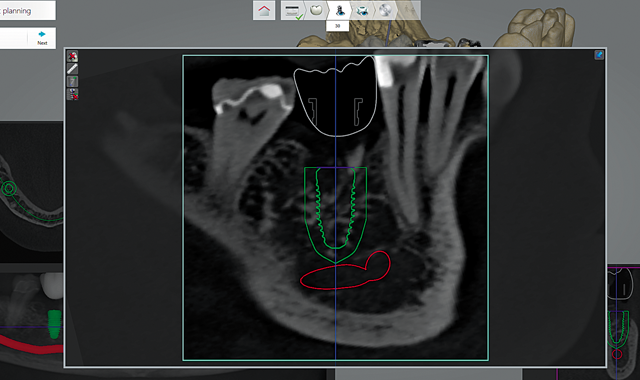

02 Once the Rx is complete, the final restoration is designed using an abbreviated set of tools and functions found in the existing 3Shape Dental System CAD software. Once the design of the restoration is complete (Fig. 3), an outline of the final restoration appears in the CBCT views throughout the planning (Fig. 4).

Fig. 4 Designed crown in the CBCT scan

Intuitively, the software places the implants extremely close to the final desired location through smart placement using the restoration design previously completed. The software currently has a 2 mm safety zone around the implant (Fig. 6).